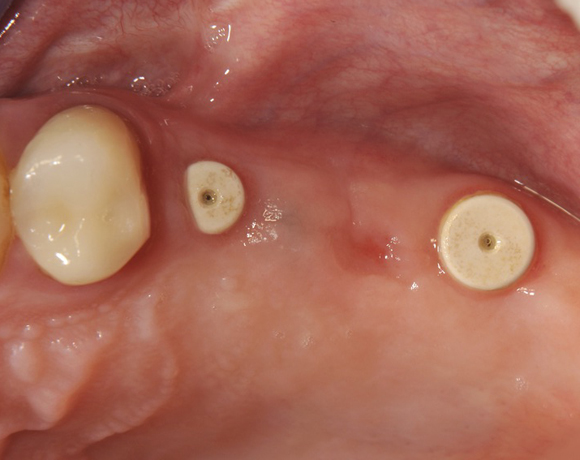

Im vorliegenden Patientenfall wurden für die Zähne 25 und 27 jeweils ein Implantat gesetzt. Nachdem die Implantate eingeheilt waren, wurde 25 – 27 mit einer Brücke versorgt.

Der operative Teil